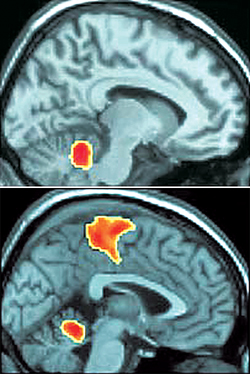

진짜 오르가슴을 느낄 때의 뇌(위)는 몸의 균형을 유지하는 소뇌를 제외한 나머지 영역이 활동을 멈춰 오르가슴을 느끼는 체할 때의 뇌(아래)와 확실히 다르다. 사진 제공 그로닝겐대

오르가슴 동안 여성의 뇌는 대부분 활동하지 않는 것으로 드러났다. 두려움과 불안에 관여하는 뇌 부위나 의식적인 행동을 담당하는 대뇌피질도 활동을 중지했다. 하지만 가짜 오르가슴 상태에서는 이 영역들이 활성화됐다.